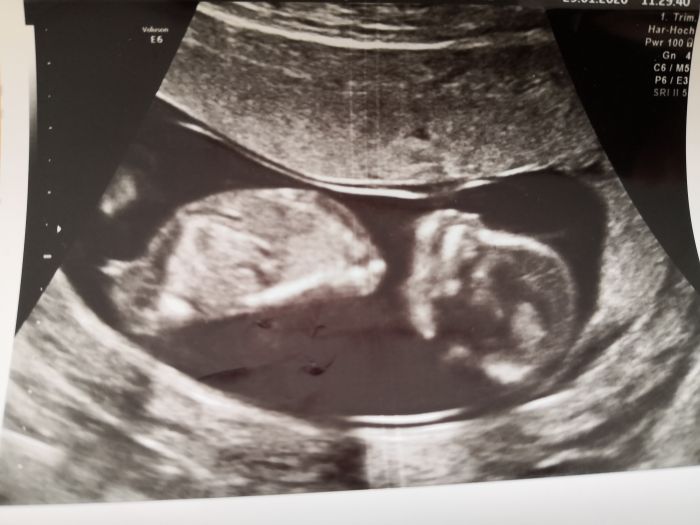

Tak mam po testech a na to jak mi je, tak baby se ma naprosto skvele. Merili sijove projasneni, max. hodnota je 2.5cm,musi provest 3 ruzna mereni, vse jsem mela v rozmezi 1.14-1.5cm.Takze rikala ze vse naprosto v klidu a ze si mysli, ze s krvi problem nebude zadny, teda ne takovy, aby to melo vyrazny vliv na vysledek. Ale konecny vysledek bude v pondeli. Po dohode mam prestat brat ten rozpustny horcik a koupila jsem si kapsle v marketu, neobsahuji tolik kyselin, takze by to nemelo tolik drazdit zaludek, jen si to musim platit sama, ale to je jedno. Plus jsem dostala neco na nevolnosti. Pozitivni je, ze vaha ne stale nizsi nez pred tehu, o coz se nebojim ze pak nedozenu

. Tlak konecne dobry. Moc mi delaly nakonec a myslim ze dobry to nebylo, dle prukazky, ale asi nic strasneho. Syn musel jit s nami, nechtel cekat v cekarne a bylo z toho utz uplne hotovy. Videl baby, kosti, baby se hybalo, pro nej velky zazitek.

Dostali jsme asi 7 fotecek. A stejne jako minule o 2 dny pred terminem. A dalsi kontrola 19.2.A pohlavi nam pry drive nez v 17tt nerekne. Ze to neni uplne jednoznacne.